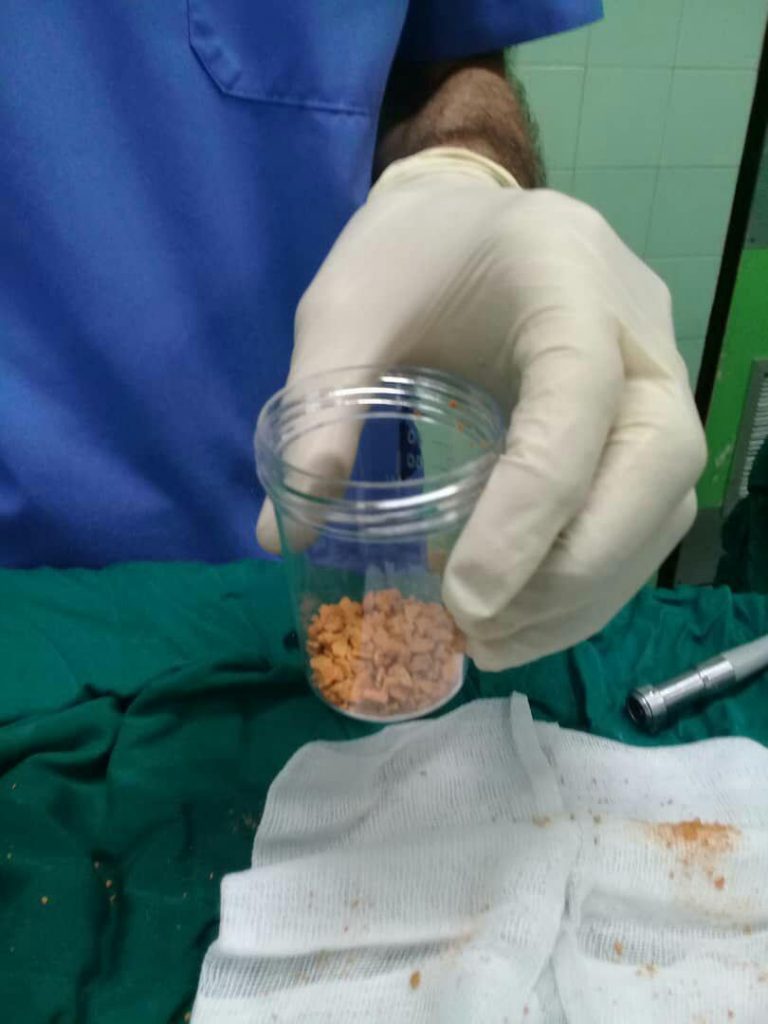

جراحی سنگ به روش بسته و PCNL

- درمان سنگ کلیه

- از بین بردن سنگ کلیه